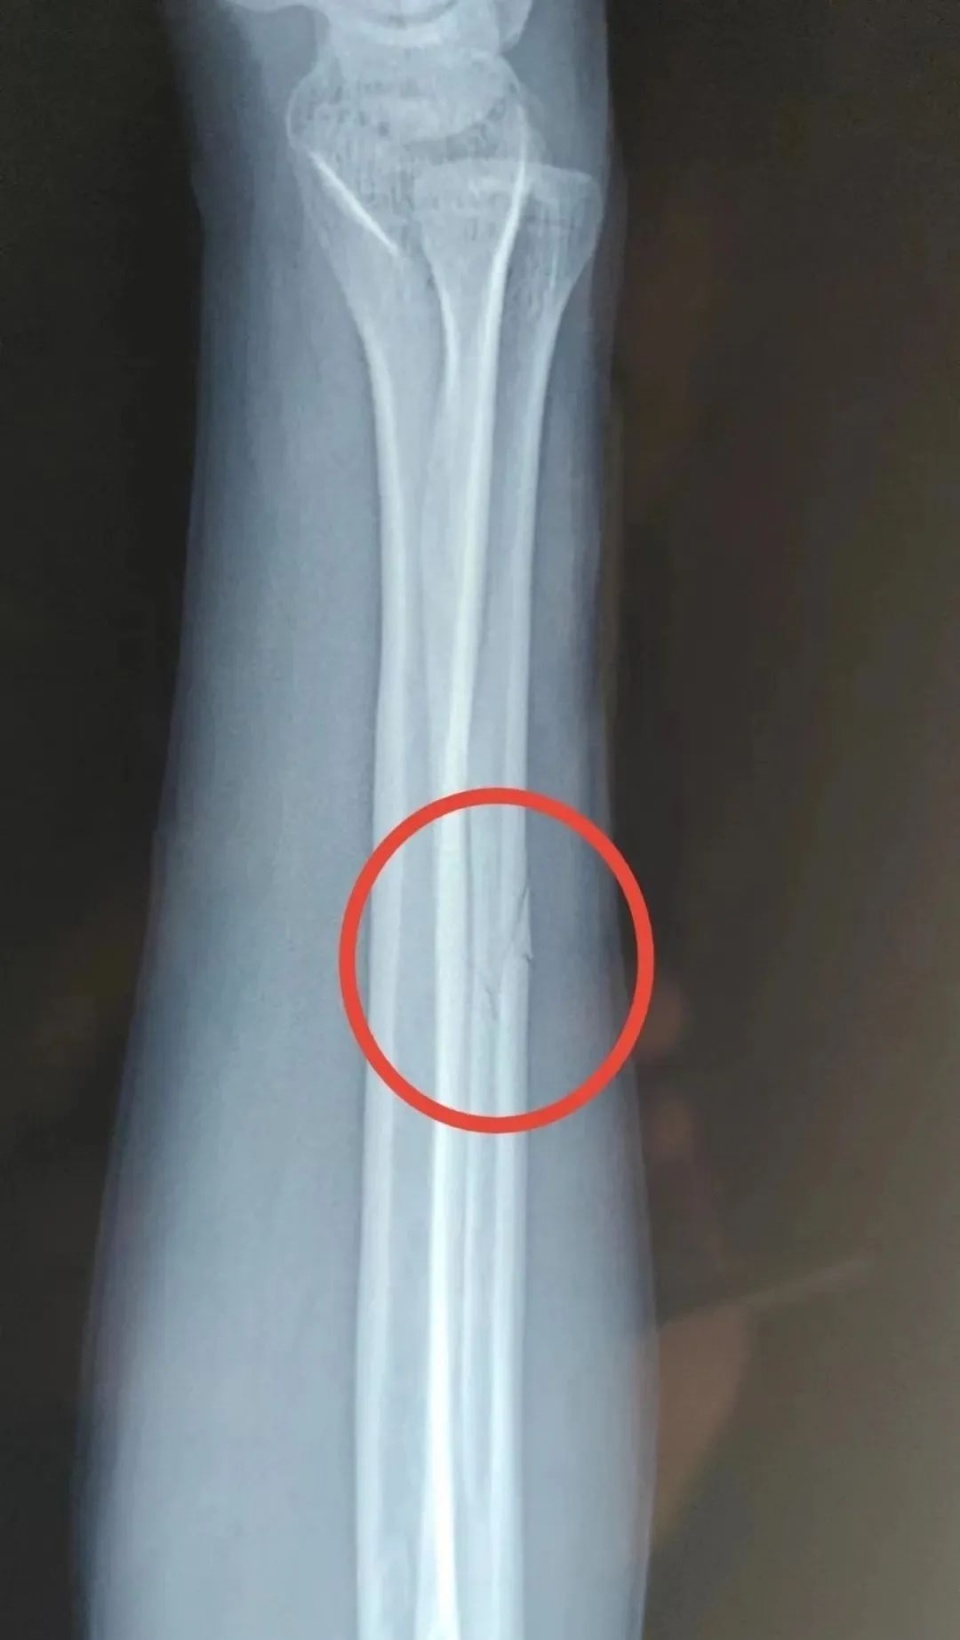

事发后宋某报了警,当晚去医院检查并打了石膏,医生让先回家观察。宋某系第二天右臂痛疼难忍,于2022年11月13日下午6时自行前往丹凤县医院检查。经诊断右尺骨骨折,外伤性头疼。